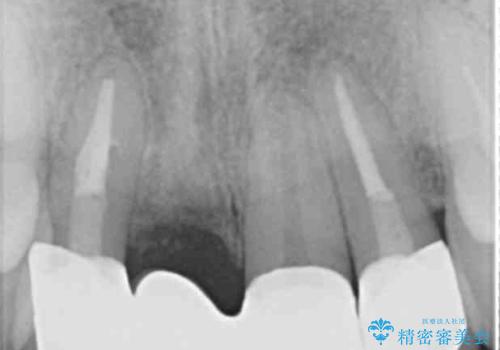

CT撮影を行った結果、右上前歯は吸収が進み抜歯が必要な状態です、

抜歯をせず放置すると、より吸収が進み臨在する歯にも悪影響を及ぼしてしまう可能性が考えられます。

上顎4前歯は、根管治療の既往があり、虫歯も見られたことからブリッジによる治療で審美性の回復を行うとともに臨在歯の虫歯もセラミック治療を行っていきます。

欠損部の歯ぐきの量が足りない場合は、移植を行い歯肉を増大させることもありますが、今回は仮歯で様子を見た結清掃性・審美性に問題が出なかったので行いませんでした。